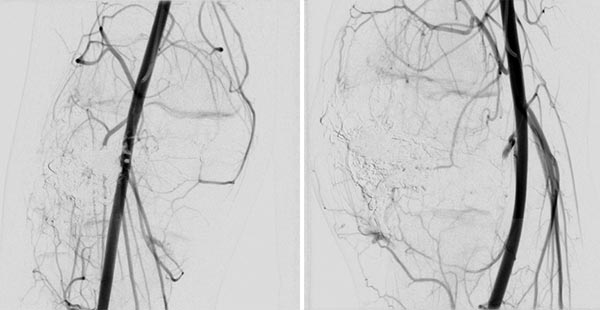

In der Kontroll-DSA (links a.-p., rechts seitlich) nach Embolisation mit Ethylen-Vinyl-Alkohol-Kopolymer zeigt sich auch in einer langen Serie keinerlei Perfusion mehr in der Angiographie. Die AVM gilt als verschlossen.